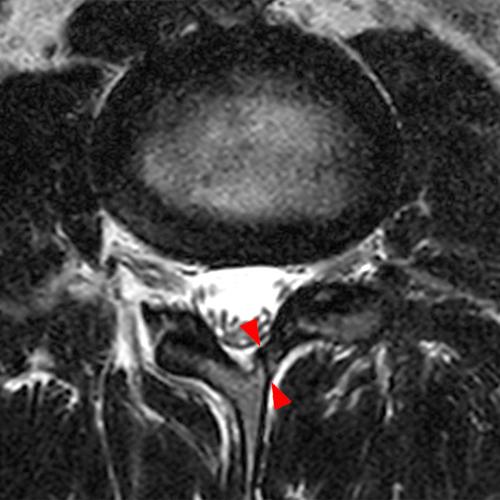

Case 2: T1-weighted (4A) and T2-weighted (4B) axial images show T1 hypointensity and T2 hyperintensity (arrowheads) in the left lamina of L5 adjacent to a small hypointense line (arrows) which traverses the lamina.

Case 2: Acute left-sided laminolysis